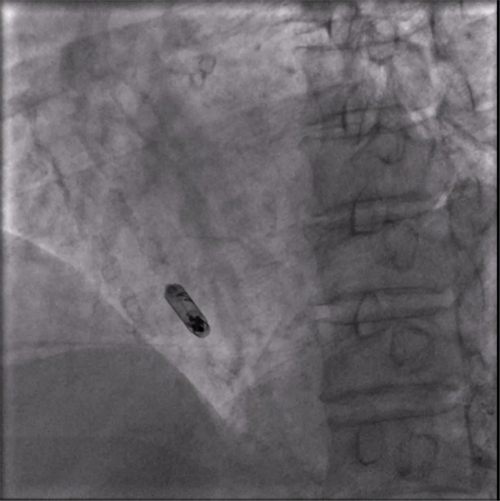

植入后右前斜

植入后左前斜

术后第二天程控结果显示:起搏参数良好,电池预估寿命:22.6年,充分显示新型主动固定螺旋无导线起搏器大电池长寿命特点。